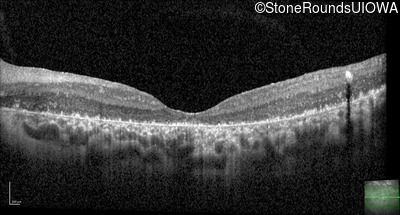

Optical Coherence Tomography - Left - 20/100 -2

Exemplar / OCT Stack